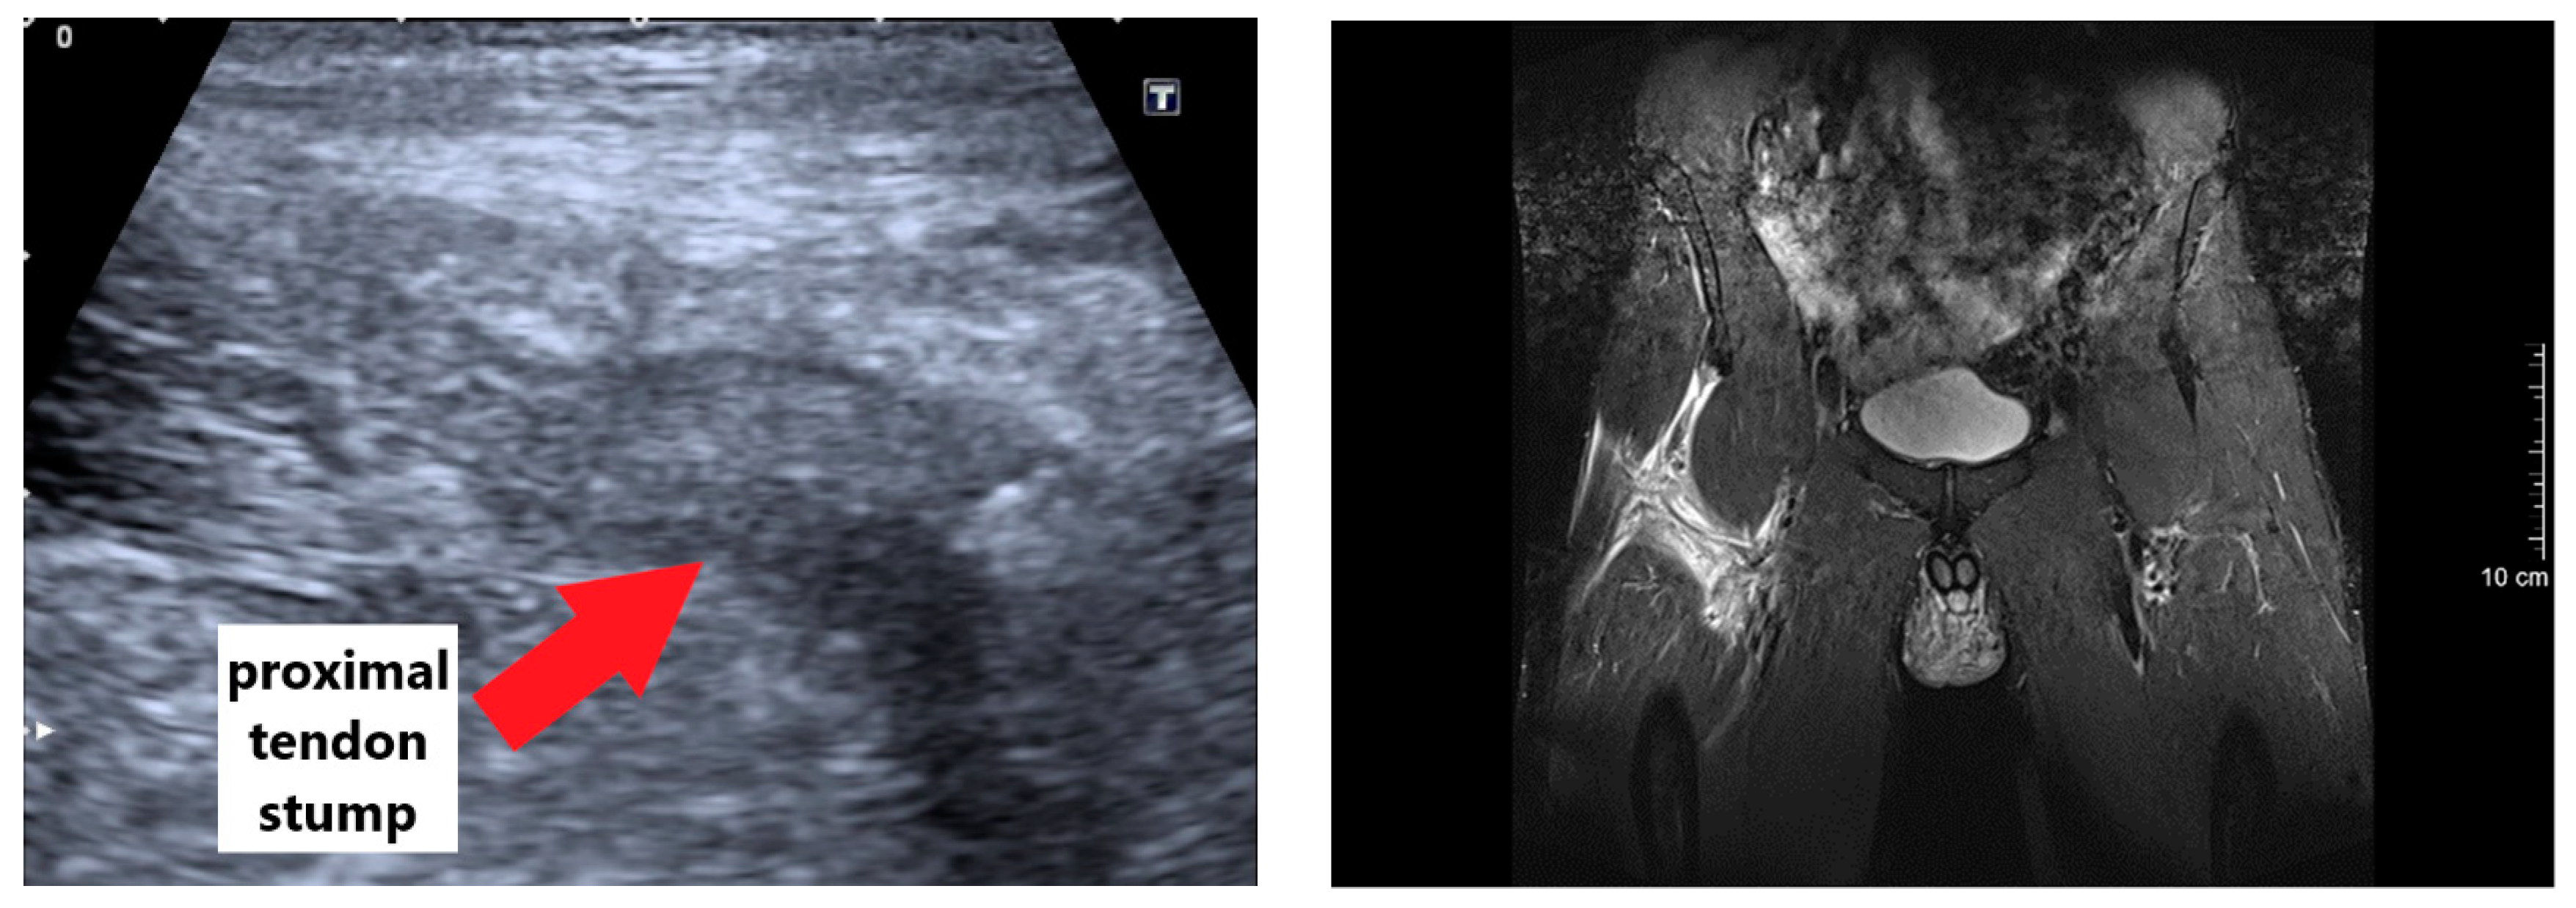

In our case report, the injury mechanism equates to one of the most commonly described injury situations in soccer [6,20]. Without the involvement of an opposing player, the kicking leg caught the ground, which leads to a sudden resistance against a forceful concentric muscle contraction [7]. This high impact change from concentric to isometric/eccentric muscle load may have overreached the maximal tolerable strain of the proximal rectus femoris muscle tendon. Within our case report, the impact of the inadequate initial treatment is unknown, but the importance of the initial therapy in muscle injuries has to be acknowledged [21]. The bearable acute pain and absence of a fall were in contrast to the severity of the injury and international muscle injury classification [16]. Thus, a fast and proper diagnosis is of crucial importance for optimal treatment. As shown in Figure 8, a safe and reliable diagnosis of a complete avulsion of the proximal rectus femoris muscle based on ultrasound images alone is difficult. As the tendon is less supplied with blood, only a small hematoma is often detectable and the severity of the injury may be underestimated [6]. However, a complete function loss, palpation of a gap, and/or retraction of the muscle during the physical examination has to be taken seriously [16]. Thereon, and as supported by our data, a fast evaluation per MRI is clearly recommend, which permits a precise localization and quantification of the injury [10,22,23]. In case of a complete avulsion of the proximal rectus femoris with a dislocation and significant retraction, a surgical treatment is recommended [24], because the effect of non-anatomical healing on muscle strength and function is currently unknown [20]. However, among other aspects, the decision has to take into account the age, previous injuries, comorbidities, and activity level of the patient. In particular, in elite athletes, a non-operative treatment may predispose the patient to a higher recurrence rate [10]. As the patient of this case study was a healthy, middle-aged, and highly active athlete, a surgical repair with a suture anchor approach was performed.

Figure 8.

Axial and coronal magnetic-resonance (right), axial and sagittal ultrasound (top left), and intraoperative (bottom left) images.